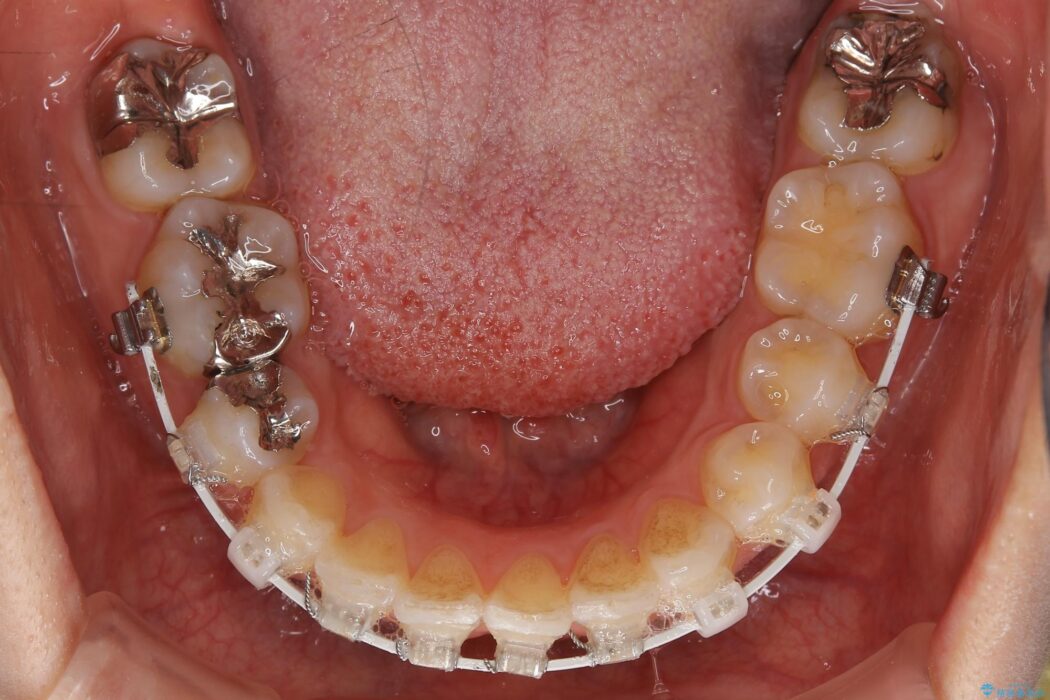

いつもでしたらマウスピース矯正をおすすめするのですが、自己管理の煩わしさから、目立たないワイヤー装置にて矯正治療を行うこととしました。

後戻りの程度としては軽度なので、治療期間としては短く終えることが出来ました。